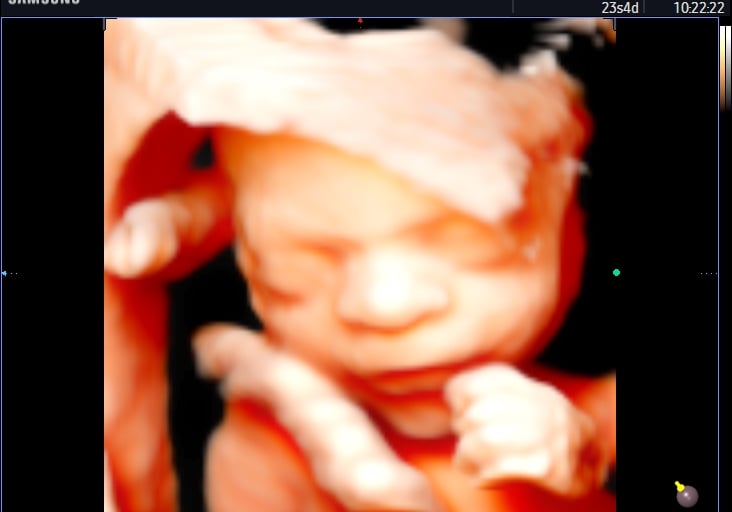

Exames de Ultrassonografia

Oferecemos ultrassonografia geral, morfológico, ecografia vascular e dermatológica com alta precisão e qualidade.